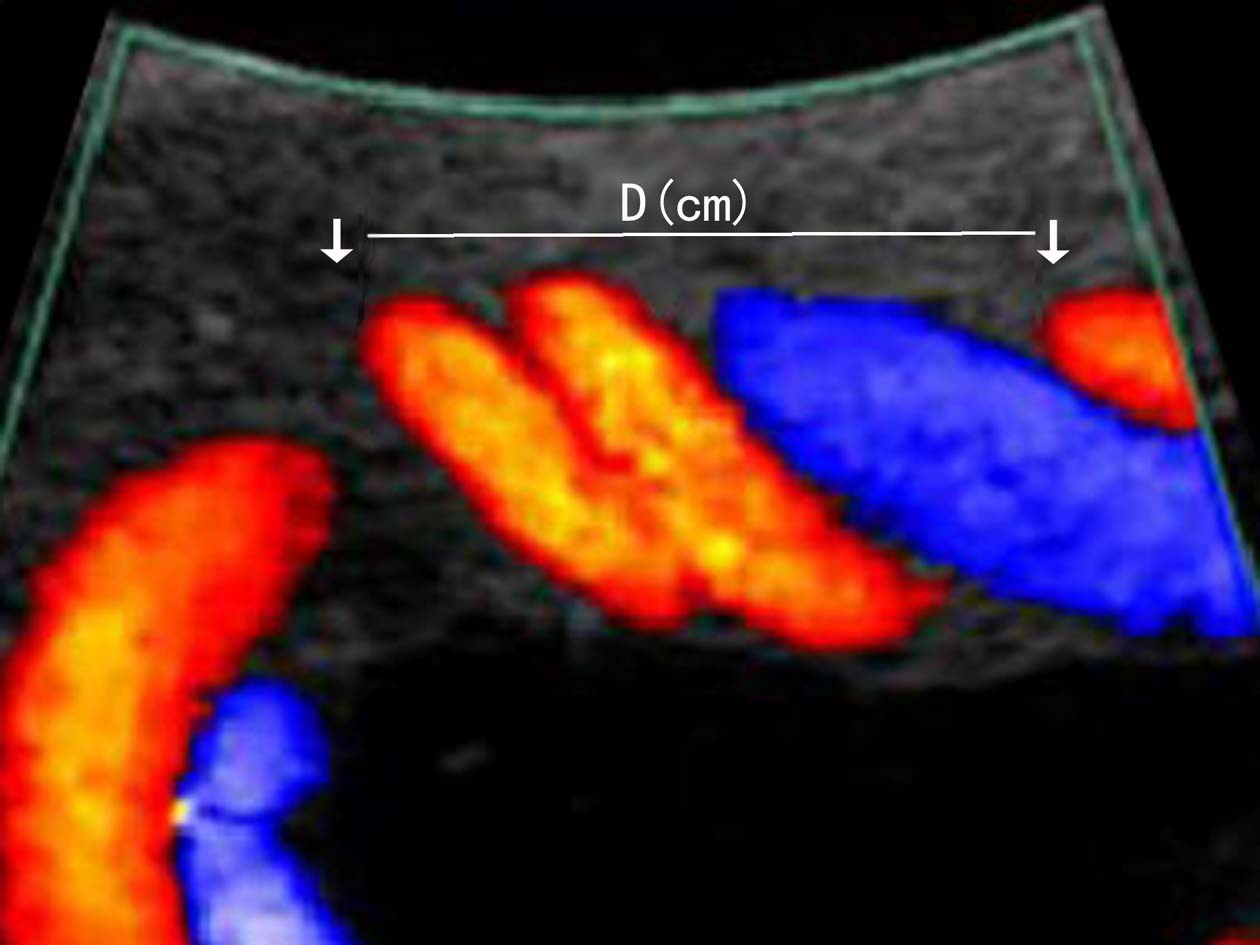

正常脐带静脉和脐带动脉呈螺旋状,形成脐带螺旋的确切原因还不清楚。但正常的脐带螺旋状态对维持胎儿运动时正常血液循环、承受一定的拉力有重要的意义。脐带螺旋可以是左旋或右旋,一般认为左旋比右旋常见,有统计左旋是右旋的7倍。可以使用每厘米长度的脐带螺旋数目——脐带螺旋指数评价脐带螺旋的程度(图4)。但不同的研究获得的螺旋指数参考值差异较大。Strong等报道的正常UCI均值为(0.21±0.07)(SD)/cm;Degani等报道为(0.44± 0.11/)cm;而van Diik等获得的UCI均值为(0.17±0.009)/cm;Coetzee AJ等对双胎妊娠进行了观察,60例单绒毛膜的UCI是0.55/cm,148例双绒毛膜双胎的UCI是0.49 /cm。

图4脐带螺旋指数计算

超声显像检查可通过测量脐带纵轴切面上两个螺旋之间的距离来计算螺旋指数,评价脐带螺旋稀少或脐带螺旋过度(图5)。超声多普勒血流显像检查时脐带过度螺旋显示血管绞合明显,脐带血管内径缩小、血流加速;螺旋稀少时显示脐带血管平直,绞合稀少。频谱多普勒检查可以对脐带动脉的血流进行评价。

图5脐带螺旋异常